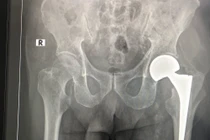

Thay khớp háng nhân tạo ở người cao tuổi luôn là một trong những thách thức đối với kíp gây mê và phẫu thuật viên. Mới đây, khoa Chấn thương chỉnh hình đã thay khớp háng nhân tạo thành công cho cụ bà 107 tuổi.

(khoahocdoisong.vn) - Bệnh viện Chợ Rẫy TPHCM đã phối hợp đa chuyên khoa tiến hành phẫu thuật thay khớp cổ xương đùi thành công cho 1 trường hợp lớn tuổi - bệnh nhân N.T.K. (106 tuổi). Đây là bệnh nhân lớn tuổi nhất được thay khớp cổ xương đùi tại Bệnh viện Chợ Rẫy TPHCM.

(khoahocdoisong.vn) - Đây là bệnh nhân cao tuổi thứ 5 trên 96 tuổi tính từ năm 2016 đến nay mà các bác sĩ khoa Chấn thương Bệnh viện đa khoa Hà Đông phẫu thuật thành công.